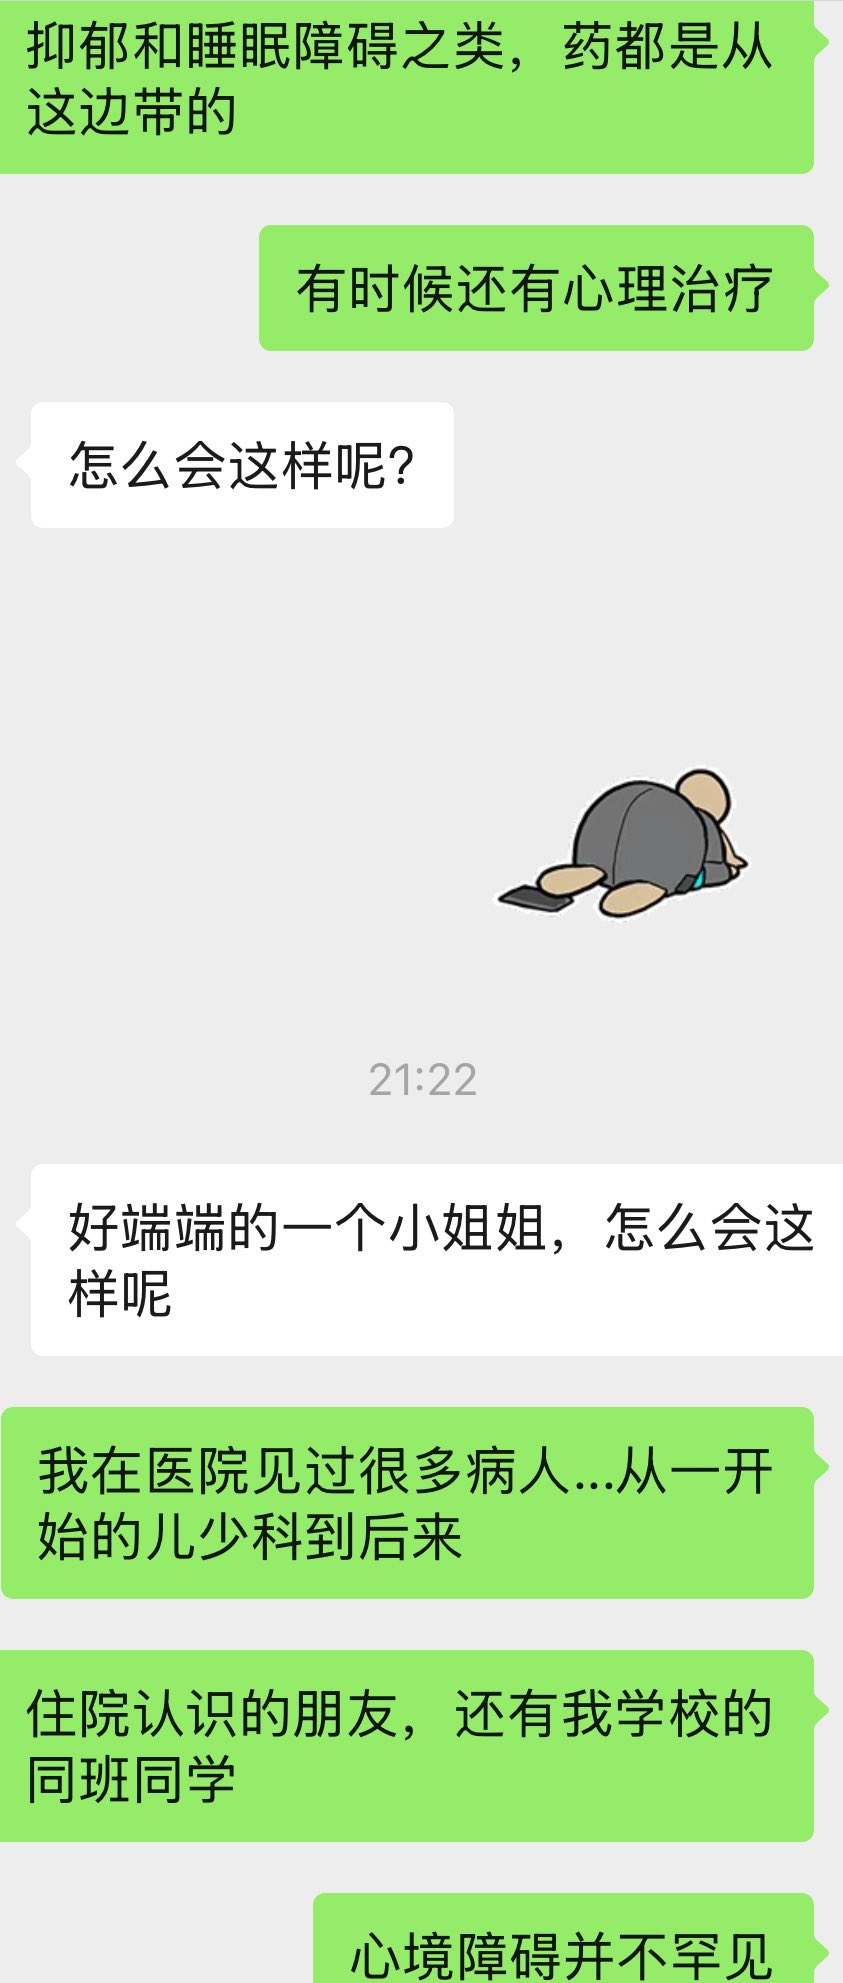

真的会推荐发作的时候或难治性抑郁做氯胺酮🥺关于价格,不算私立医院或住院的情况,一般一次是800...其实以前药费也有吃到过很高

不会像mect那样副作用很可怕,我的感觉是几乎没有负面影响

顺着这个思路用的auv对我效果也很好。那么漫长的寻找和尝试总算有了相对稳定的解法..太好了